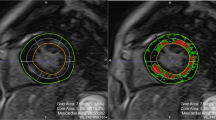

Although echocardiography remains the mainstay imaging technique for the evaluation of patients with valvular heart disease (VHD), innovations in noninvasive imaging in the past few years have provided new insights into the pathophysiology and quantification of VHD, early detection of left ventricular (LV) dysfunction, and advanced prognostic assessment. The severity grading of valve dysfunction has been refined with the use of Doppler echocardiography, cardiac magnetic resonance (CMR), and CT imaging. LV ejection fraction remains an important criterion when deciding whether patients should be referred for surgery. However, echocardiographic strain imaging can now detect impaired LV systolic function before LV ejection fraction reduces, thus provoking the debate on whether patients with severe VHD should be referred for surgery at an earlier stage (before symptom onset). Impaired LV strain correlates with the amount of myocardial fibrosis detected with CMR techniques. Furthermore, accumulating data show that the extent of fibrosis associated with severe VHD has important prognostic implications. The present Review focuses on using these novel imaging modalities to assess pathophysiology, early LV dysfunction, and prognosis of major VHDs, including aortic stenosis, mitral regurgitation, and aortic regurgitation.

Barone-Rochette, G. et al. Prognostic significance of LGE by CMR in aortic stenosis patients undergoing valve replacement. J. Am. Coll. Cardiol. 64, 144–154 (2014).

Dweck, M. R. et al. Midwall fibrosis is an independent predictor of mortality in patients with aortic stenosis. J. Am. Coll. Cardiol. 58, 1271–1279 (2011).

Mewton, N., Liu, C. Y., Croisille, P., Bluemke, D. & Lima, J. A. Assessment of myocardial fibrosis with cardiovascular magnetic resonance. J. Am. Coll. Cardiol. 57, 891–903 (2011).

Singh, A. et al. Myocardial T1 and extracellular volume fraction measurement in asymptomatic patients with aortic stenosis: reproducibility and comparison with age-matched controls. Eur. Heart J. Cardiovasc. Imaging 16, 763–770 (2015).

de Meester de Ravenstein, C. et al. Histological Validation of measurement of diffuse interstitial myocardial fibrosis by myocardial extravascular volume fraction from Modified Look-Locker imaging (MOLLI) T1 mapping at 3 T. J. Cardiovasc. Magn. Reson. 17, 48 (2015).